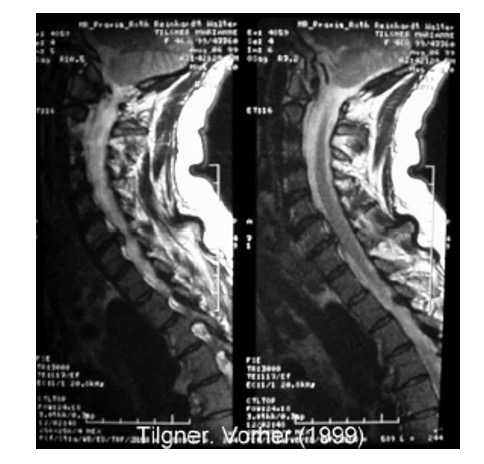

Эффективность лечения оценивалась по данным клинического наблюдения, показаниям электрофизиологических исследований: рентгенографии (включая рентгенографическую компьютерную томографию и магнитно-резонансную томографию (рис. 21а, 21б, 22а, 22б)), параметрам функции внешнего дыхания, показателям гемодинамики при реоэнцефалографии и лазерной допплерографии, компьютерно-оптической топографии позвоночника, электроэнцефалографии, результатам измерения величины электрокожного сопротивления в репрезентативных точках акупунктуры, стабилометрии и др. У всех пациентов независимо от основной патологии при мануальном обследовании выявлены функциональные блокады ПДС, напряжение различных групп мышц (прежде всего в мышцах верхнего плечевого пояса) и наличие в них болевых точек. Выраженность болевого синдрома оценивали по визуально-аналоговой шкале (ВАШ), выраженность тревожной и депрессивной симптоматики определяли по шкале А. Бека.

Рис. 22. Магнитно-резонансная томограмма шейного отдела позвоночника при болевом синдроме

а) ДО проведения Детензор-терапии отмечается секвестрированная грыжа межпозвонкового диска с компрессией дурального мешка

б) ПОСЛЕ проведения Детензор-терапии отмечается очевидный регресс грыжи межпозвонкового диска